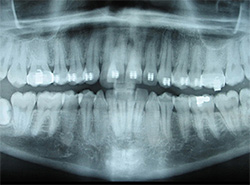

Digital X-Rays

Using the most advanced dental technology possible is just as important as staying up-to-date on the latest treatment techniques. Because our practice is dedicated to providing you with the safest and most convenient treatment options available, we utilize advanced digital X-ray technology in our office.

Digital X-rays provide several advanced imaging options, designed to save time, provide clearer dental photos, and expose patients to less radiation than with traditional X-ray technology.